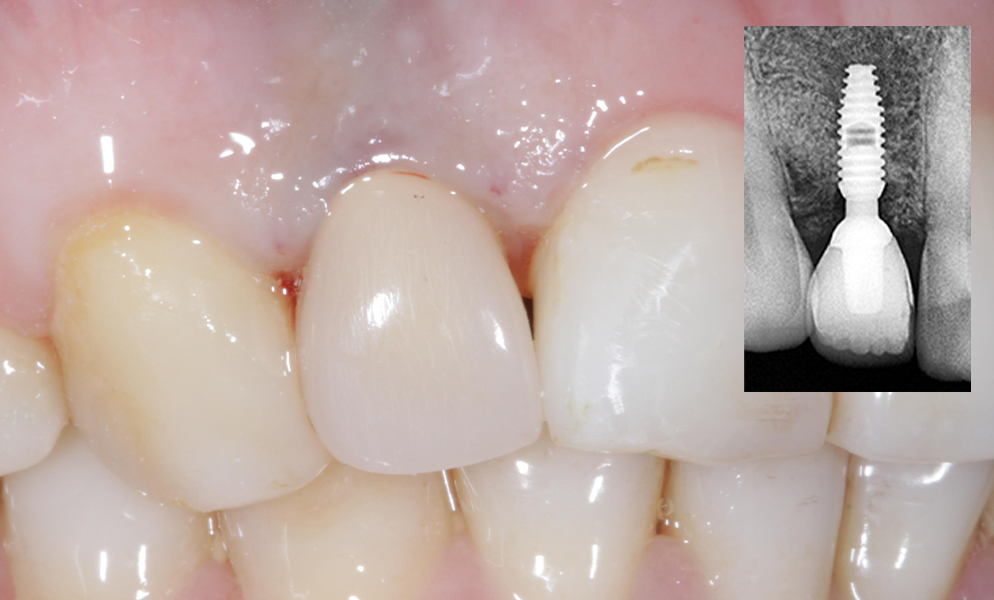

![]() |

| Single anterior tooth missing space restored with a narrow dental implant (Bicon, USA) | |